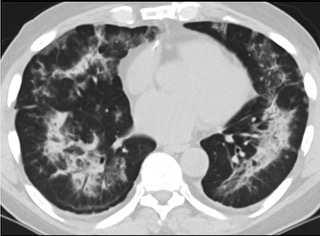

6天后的軸向CT平掃圖像顯示毛玻璃影變為實變和輕度結構扭曲。(同一病人CT影像)

16位被文獻報道為電子煙肺炎的患者被專家判定為“病毒性感染”,即有可能是新冠肺炎的“疑診患者”,其中更有5位臨床癥狀和治療情況相對完整的患者被判定為“中度可疑”。因此在2019年美國報道的電子煙肺炎中存在病毒性感染的病例,而且不排除美國電子煙肺炎中存在新冠肺炎的可能性。